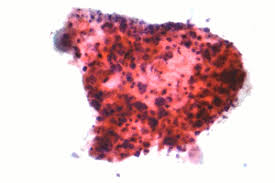

Lung Cancer Signs And Symptoms Tagalog : What Are The Symptoms And Signs Of Ovarian Cancer Ctca : Hemoptysis can occur in lung cancer, bronchitis, pneumonia, tuberculosis, injuries, and some cardiovascular conditions.. Doctors call this collection of symptoms carcinoid syndrome and it is more likely to occur if the lung net has spread to other parts of the body, particularly the liver. Knowing the early warning signs of lung disease can help you receive treatment before the disease becomes serious or even life threatening. Common lung cancer symptoms often, when patients receive a lung cancer diagnosis, they have been experiencing symptoms such as persistent breathing difficulty, recurring respiratory infections or chest pain for a while. It's the most common symptom of lung cancer, according to a. It can also appear as infiltrates, which look like pneumonia, but do not resolve with antibiotics — or other abnormal findings in the lung.

Lung Cancer from www.froedtert.com As is the case for many cancers, it's likely you won't notice symptoms until the lung cancer is in an advanced stage. Common lung cancer symptoms often, when patients receive a lung cancer diagnosis, they have been experiencing symptoms such as persistent breathing difficulty, recurring respiratory infections or chest pain for a while. Recognizing these signs and seeing a medical professional early on can help prevent cancer or more effectively treat it. A person suffering from lung carcinoid tumor shows signs of the illness because of the hormones entering the bloodstream, bypassing the liver. One of the symptoms of lung cancer is persistent cough. Because there are very few nerve endings in the lungs, a tumor could grow without causing pain or discomfort. It is important to pay attention to these symptoms as they could be the first signs of lung disease, including copd, asthma and lung cancer. Lung cancer is cancer that forms in tissues of the lung, usually in the cells that line the air passages.